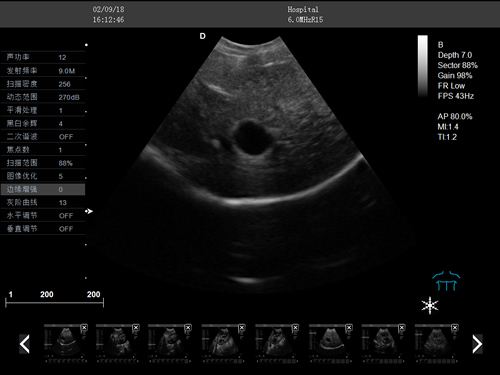

動物寵物超聲診斷儀

彩色多普勒動物超聲診斷儀

·中小動物的肝、膽,脾、腎、膀胱、子宮、妊娠等各組織器官的檢查和病變的診斷